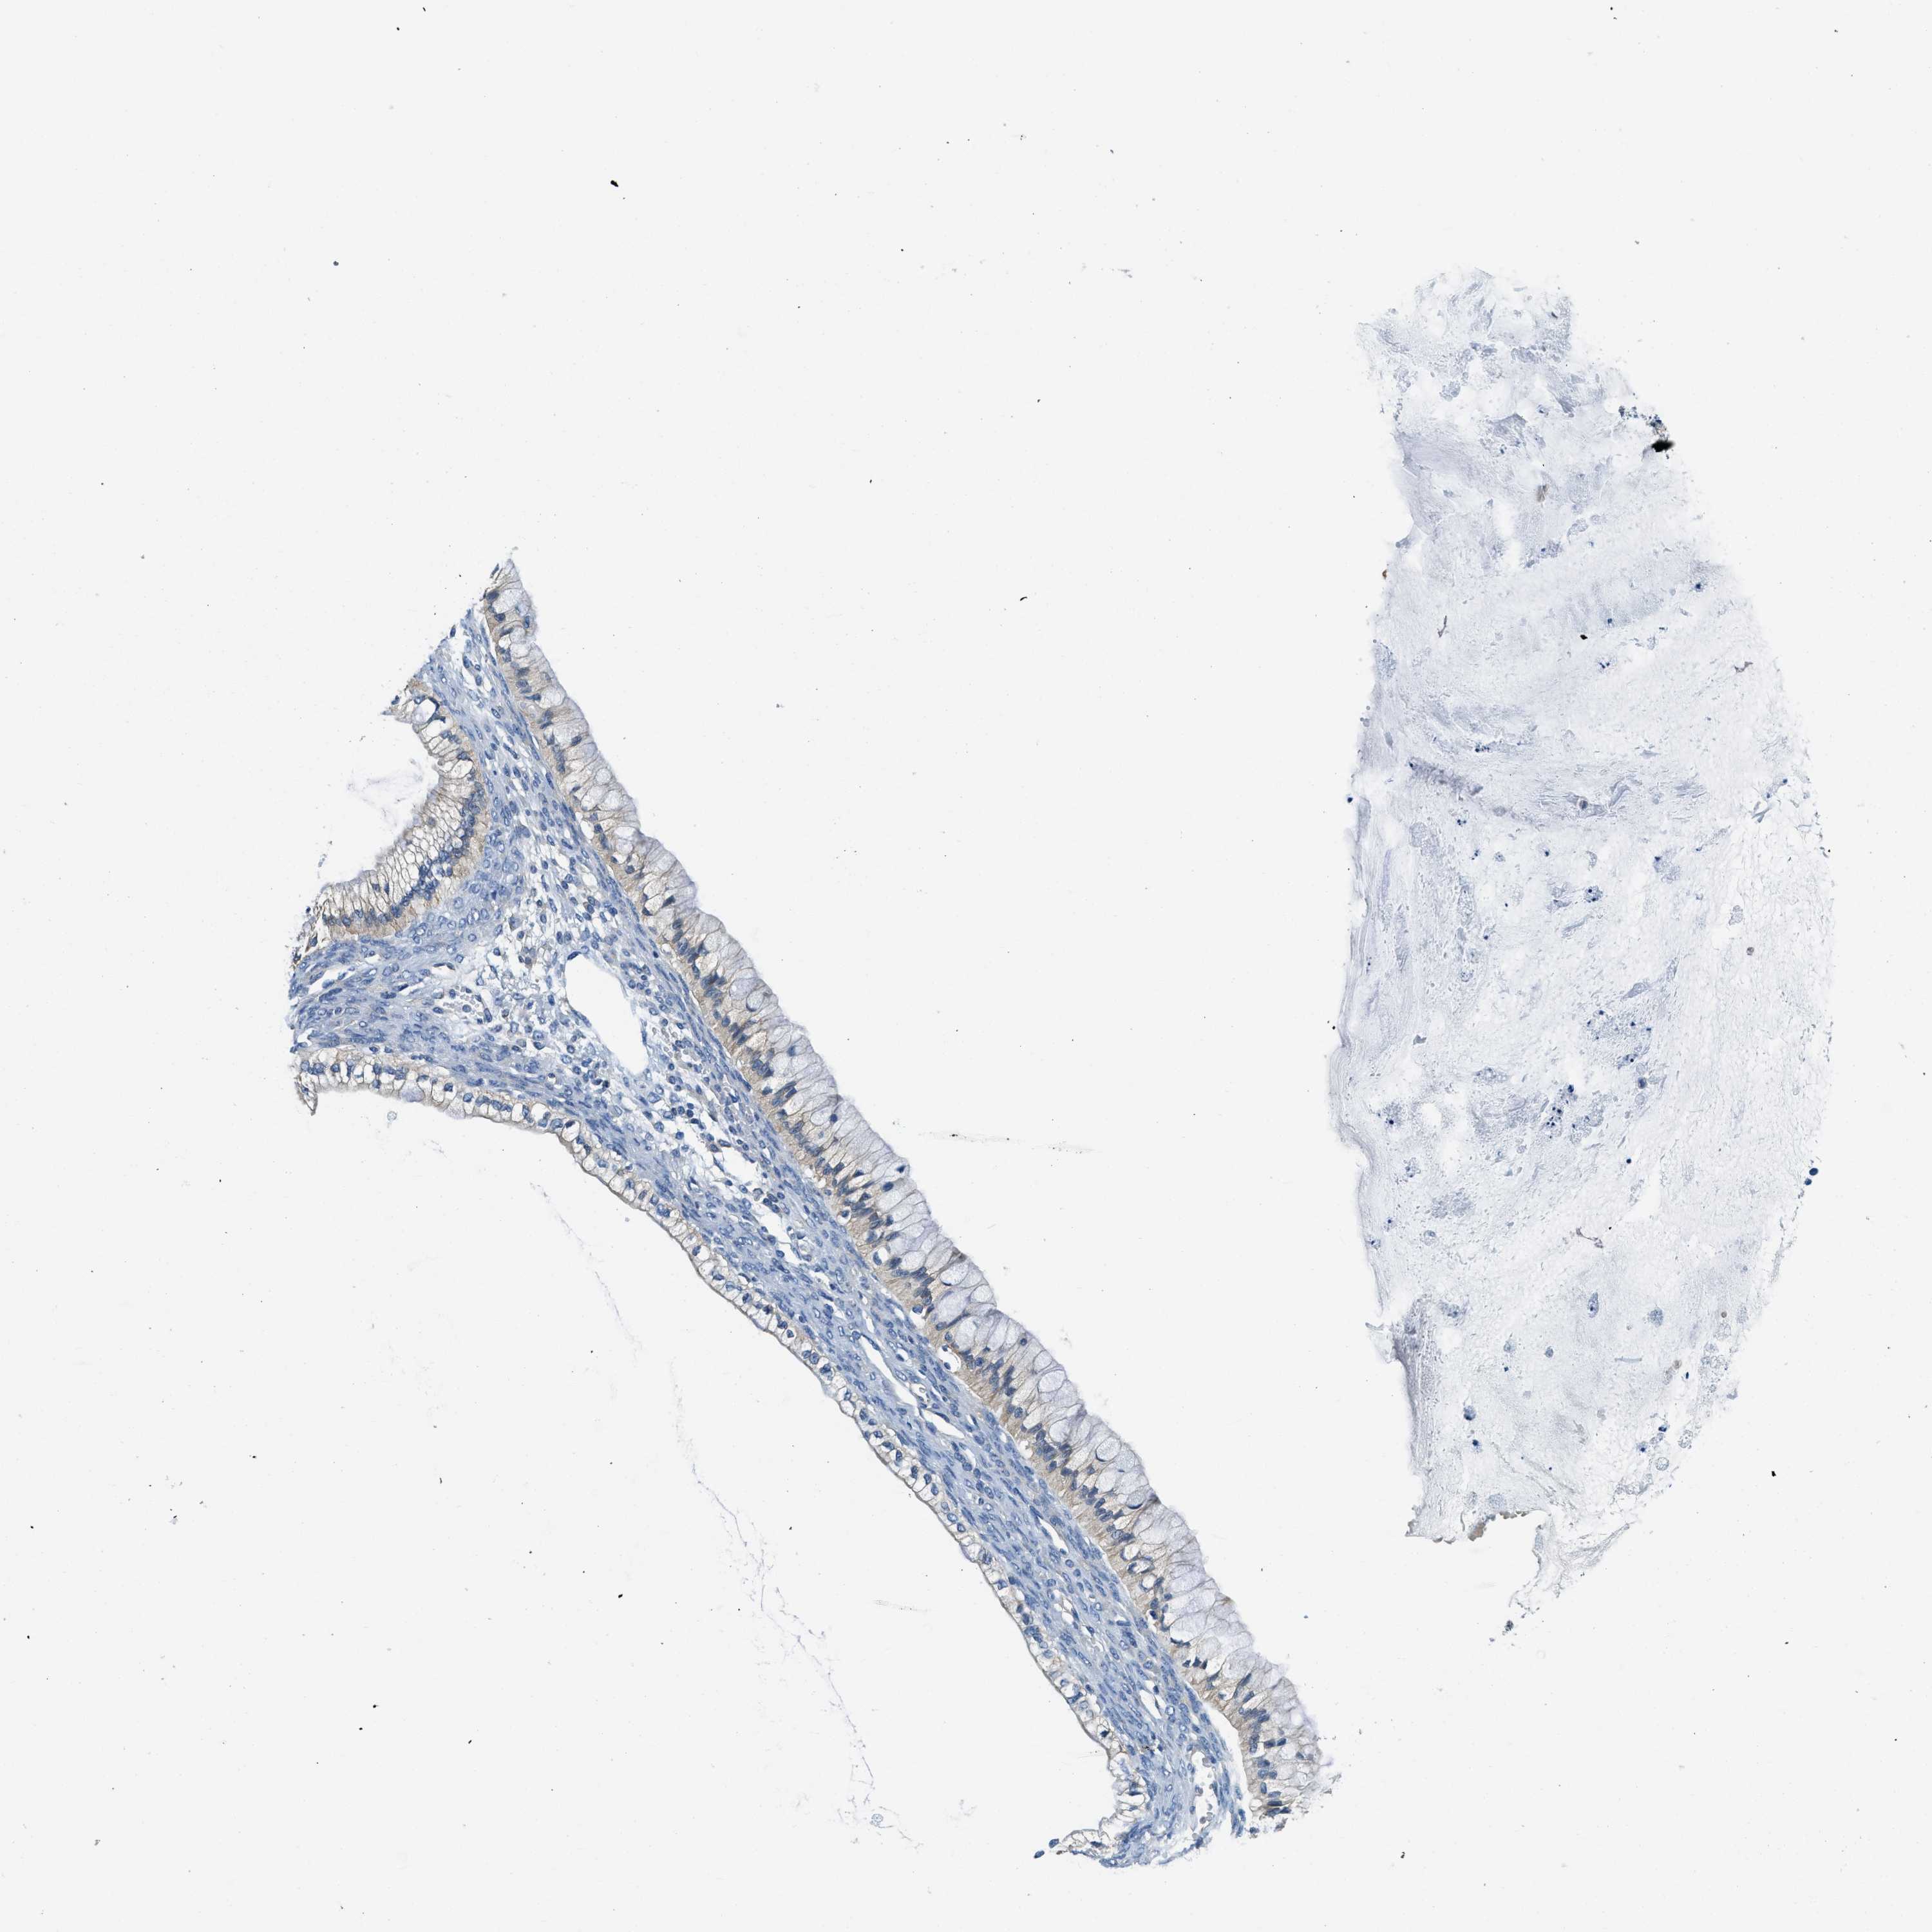

OVARIAN CANCER - Protein expressioni

A mouse-over function shows sample information and annotation data. Click on an image to view it in a full screen mode. Samples can be filtered based on level of antibody staining by selecting one or several of the following categories: high, medium, low and not detected. The assay and annotation is described here.

Note that samples used for immunohistochemistry by the Human Protein Atlas do not correspond to samples in the TCGA dataset.

Antibody stainingi

Antibody staining in the annotated cell types in the current human tissue is reported as not detected, low, medium, or high, based on conventional immunohistochemistry profiling in selected tissues. This score is based on the combination of the staining intensity and fraction of stained cells.

Each image is clickable and will lead to virtual microscopy that enables deeper exploration of all samples and also displays staining intensity scores, fraction scores and subcellular localization as well as patient and tissue information for each sample.

Antibody HPA018116

Staining

High

Medium

Low

Not detected

Intensity

Strong

Moderate

Weak

Negative

Quantity

>75%

75%-25%

<25%

None

Location

Nuclear

Cytoplasmic/membranous

Cytoplasmic/membranous,nuclear

Cystadenocarcinoma, serous, NOS

Carcinoma, endometroid

Cystadenocarcinoma, mucinous, NOS

Carcinoma, NOS